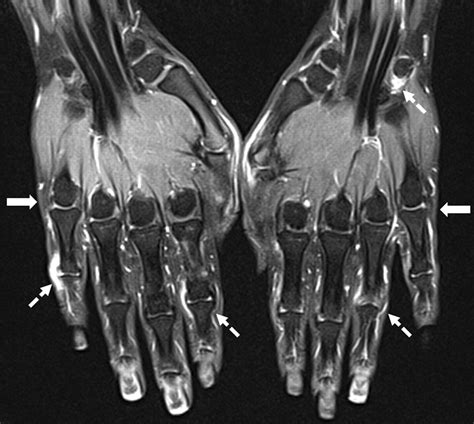

Common Findings in an MRI of Hand

An MRI of hand can reveal a variety of conditions and injuries. Some of the most common findings include:

• Fractures: Detailed images of bone fractures, including hairline fractures that may not be visible on X-rays.

• Tendon Injuries: Tears or inflammation in the tendons, which can cause pain and limited mobility.

• Ligament Injuries: Tears or sprains in the ligaments, which can affect joint stability.

• Arthritis: Signs of joint degeneration, inflammation, and bone spurs.

• Carpal Tunnel Syndrome: Compression of the median nerve in the wrist, causing numbness and tingling in the hand.

• Tumors and Cysts: Benign or malignant growths within the hand tissues.